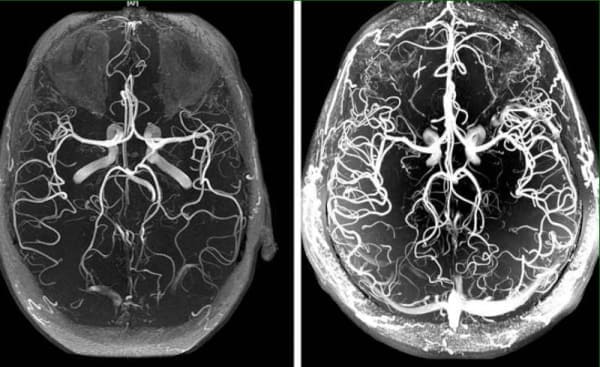

Miya tomirlarining angiodistoniyasi patologik holat bo'lib, unda tomirlar tonusi va miya to'qimalarida normal qon aylanishi buziladi. Ushbu maqolada siz uning sabablari, mexanizmlari va alomatlari haqida ogohlantirish vaqti kelganini o'qishingiz mumkin. Shuningdek, ushbu hiyla-nayrangli kasallikning dahshatli asoratlari va davolanishga zamonaviy yondashuv hamma uchun mavjuddir.

Miya tomirlarining angiodistoniyasi butun organizmning ishiga ta'sir qiladi. Miyaning qon bilan etarli darajada ta'minlanmaganligi sababli, umumiy ishlash pasayadi, zaiflik paydo bo'ladi va muhim tana tizimlari ishlamay boshlaydi.